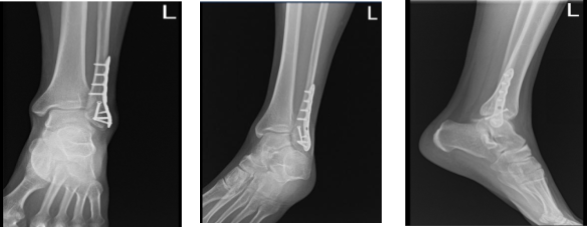

After weeks the patient went back to the office for his follow up checkup, with an x-ray of his ankle for review. He denies fever, chills, pain and he is WBAT with boots, no crutches. X-rays were reviewed and discussed, there is a surgically treated fracture distal left fibula.

A faint fracture line is visualized, the visualized distal left tibia is unremarkable and visualized aspects of the left talus, calcaneus and tarsal bones demonstrate intact cortical margins with no evidence of an acute fracture.

Ankle mortise is well maintained however, there is mild soft tissue swelling laterally and no calcaneal plantar spur.

Left ankle X-ray complete 3 (2)

Left ankle X-ray complete 3